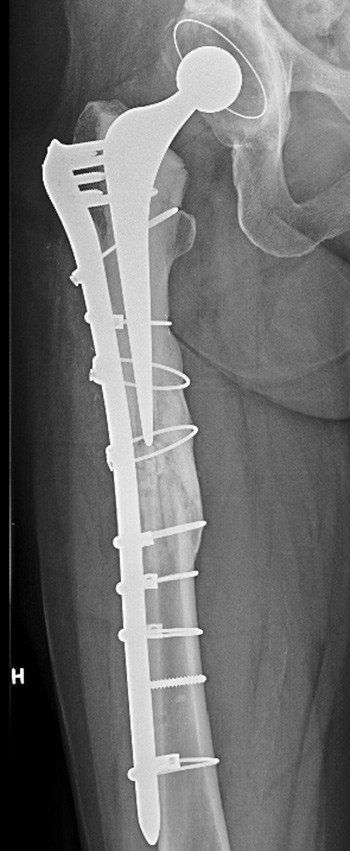

It is widely agreed that the optimal treatment for periprosthetic femoral fractures following hip arthroplasty is internal fixation (3). The Swedish Hip Arthroplasty Register reports a 34 % failure rate of osteosynthesis for this type of fracture. When, in addition, the fractures are atypical, the rate of complications may conceivably be even higher. Atypical femoral fracture that occurs periprosthetically has, to our knowledge, not been discussed previously. This further increases the uncertainty with regard to prognostic assessment and choice of treatment.

Specially designed plates that provide dynamic compression and permit angle-stable placement of the screws at different angles on the plate ensure structural stability and prevent the implant from coming into conflict with prosthetic components or the cement mantle. Alternatively, cerclage cable can replace one or more of the screws. In the last decade, a plate system has also been developed that makes it possible to connect small end plates to the main plate, proximally and/or distally, to cover the entire length of the femur. Adequate fixation of the fracture can be achieved using these implants combined with structural, cortical transplants shaped like plates, and use of cancellous bone transplants (bone chips).

This treatment strategy was first implemented in its entirety when the surgical revisions were performed on our patient, and eventually resulted in healing of the fractures.

Frakturlinjen ved atypiske frakturer er oftest helt horisontal eller viser en vinkling på maksimalt 30 grader (2). Figur 1 i artikkelen viser imidlertid en frakturlinje som har en vinkel som er over 30 grader, slik at jeg ikke mener den kan klassifiseres som atypisk. Jeg mangler også i den forbindelse opplysninger om skjelettstatus hos denne pasienten med multiple brudd. Hadde den langvarige bisfosfonatbehandling hatt effekt eller var pasienten fortsatt osteoporotisk? Hvis sistnevnte var tilfellet, burde man ha overveiet osteoanabol terapi med PTH, som pasienten kunne få på blå resept.